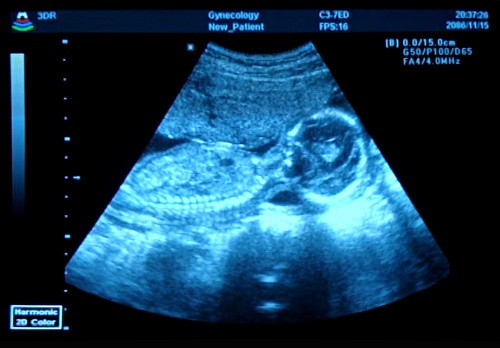

Sprawę do Trybunału wniosła kobieta o inicjałach RR w 2002 roku. Gdy była w 18 tygodniu ciąży lekarz zaczął podejrzewać, że jej czekające na urodzenie dziecko może cierpieć na zespół Turnera – wadę genetyczną powodującą m.in. upośledzenie wzrostu. Mimo licznych prób, matka nie otrzymała skierowania na genetyczne badania prenatalne, potwierdzające wadę nienarodzonego dziecka. Nie uzyskała też zgody na dokonanie aborcji w szpitalu. Urodziła chorą córkę.